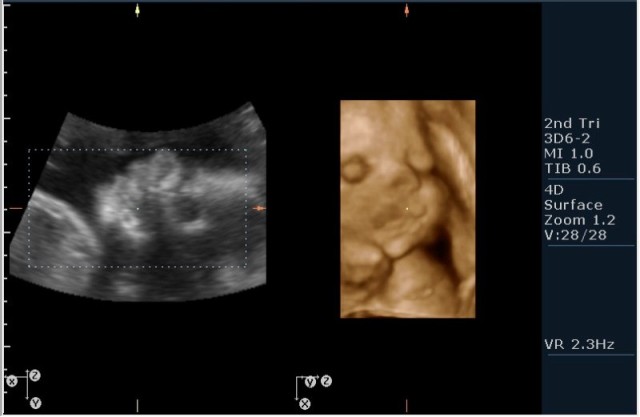

1.Вентрикуломегалия/гидроцефалия (на сонограмме №1 размер задних рогов боковых желудочков 16мм при норме до 10 мм включительно;

На сонограммах головы плода визуализаируется гифдроцефалия, патогенетически связанная со спинномозговой грыжей (менингомиелоцеле) представленная в 2D и 3D режимах. В режиме Skeleton не удалось получить "картинку презентационного качества", плод начал сильно вертется; но рекоммендация очень грамотная :idea: , спасибо за ваш пост!